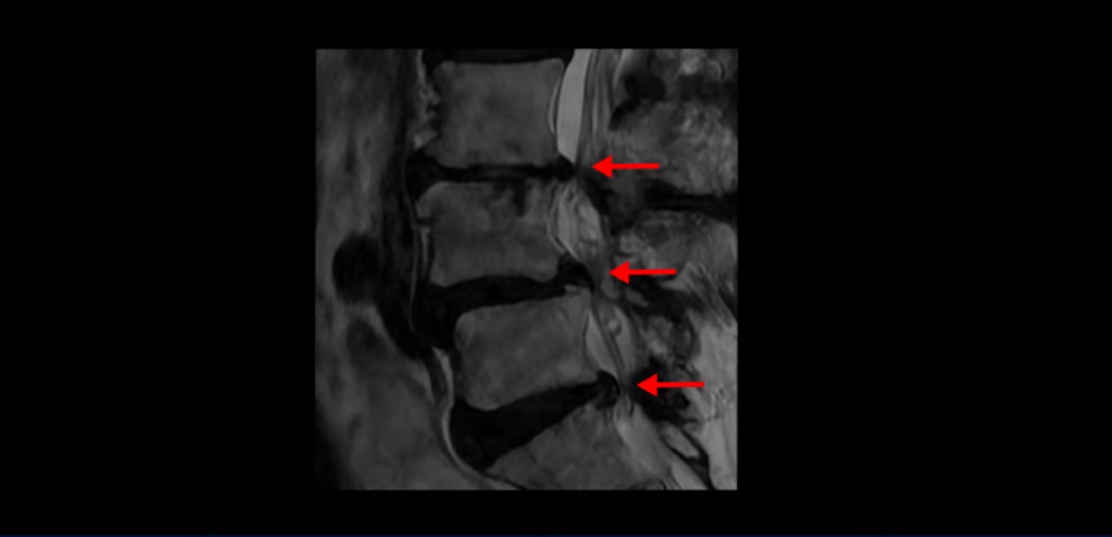

제가 먼저 이분 MRI를 보고 설명해 드린 후 어떻게 이런 분들을 수술 없이 허리 기능재활치료로 호전시킬 수 있는지 자세히 설명드리겠습니다. 이분 허리가 보시다시피 여러 마디가 퇴행되어 있고

4번 5번에는 뼈가 밀려 나간 전방전위증도 있습니다.

4번 5번 마디를 자세히 보면 심한 중심성 협착이 있어서 신경 구멍이 매우 좁아져 있습니다.

또 신경 가지가 빠져나가는 추간공도 매우 좁아져 있습니다.

그래서 양쪽 엉덩이가 아프고 다리는 발바닥까지 저리고 아프면서 발을 줄로 묶어놓은 것 같고 다리의 힘도 빠져 걷기가 어렵습니다.